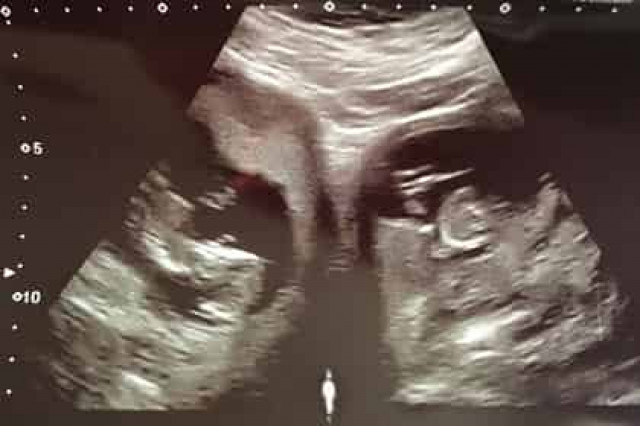

Эшвуд рассказала, что у нее уже есть ребенок, и во время первой беременности никто не заметил особенностей строения ее организма. Во второй раз женщина отправилась на плановый осмотр на 20 неделе беременности, когда врач обнаружил, что у нее не одна, а сразу две матки, и в обеих развивается по плоду.

Британка родила на 34-й неделе сына Пирана и дочь Поппи через кесарево сечение. Близнецы родились без каких-либо отклонений.

Подобное явление называют бикорнуальной маткой. Обычно женщины с такой патологией вынашивают одного ребенка в одном из органов.Вероятность оплодотворения сразу двух маток составляет 500 миллионов к одному. Всего таких случаев зафиксировано не более сотни за все время существования человечества.